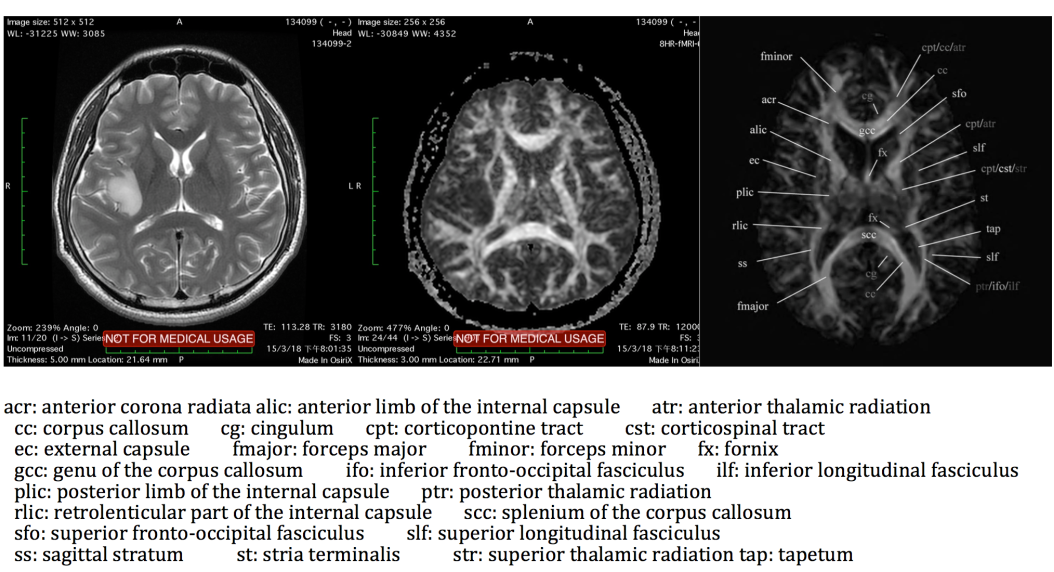

术前磁共振:

肿瘤位于左中央前回中端偏腹侧,长T1长T2,无明显强化,低灌注

解剖-中央叶-神经(皮质-皮质下)、血管(动脉、静脉)